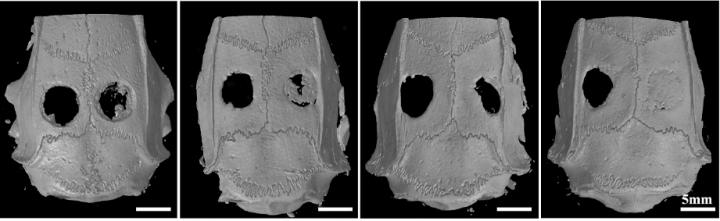

Researchers from Shanghai Jiao Tong University have developed a technique that produces 3D bioprinted bone-repair "scaffolds" that are infused with bone marrow stem cells, bone morphogenic protein-4 and macrophage.

Researchers at Laboratory of Orthopaedic Implants at Shanghai Jiao Tong University have come up with a recipe to meet the requirements. They load the bio-inks with bone marrow mesenchymal stem cells, bone morphogenetic proteins-4 (BMP-4) and the macrophage to rescue dysregulated inflammation. In addition, to extend the period over which the bone formation can occur, they added a drug delivery system to the recipe: mesoporous silica nanoparticles--inorganic nanoparticles that have been used for the delivery of drugs.

In the follow-up research, the researchers aim to design and print a biological scaffold with an improved pore structure to permit even better blood flow inside the scaffold, which should boost immune system regulation, and better promote development of both bone and blood vessels. With these additional effects, the technique will accelerate bone repair still further.